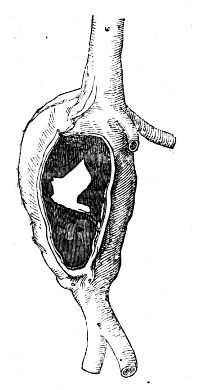

| Aneurism | 118 |

| Aneurismby Anastomosis | 127 |